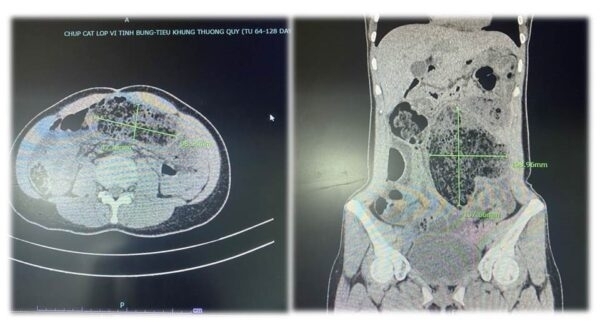

Bệnh nhân T.N.S, 62 tuổi, tỉnh Vĩnh Phúc trước đó đi khám bệnh được chẩn đoán xơ gan, viêm dạ dày. Tuy nhiên, thay vì uống thuốc theo đơn của bác sĩ người bệnh lại nghe theo trên mạng internet mua thuốc nam không rõ nguồn gốc về uống trong nhiều ngày. Sau khi uống, xuất hiện tình trạng mệt mỏi, vàng da, ăn uống kém, đầy tức bụng.

Ông S. được chuyển đến Khoa Hồi sức tích cực - chống độc, Bệnh viện ĐK tỉnh Phú Thọ trong tình trạng suy đa tạng. Các bác sĩ xác định, nguyên nhân gây suy đa tạng là do người bệnh sử dụng thuốc nam không rõ nguồn gốc dài ngày.

Ngay lập tức, các bác sĩ Bệnh viện ĐK tỉnh Phú Thọ thực hiện các biện pháp hồi sức chuyên sâu, như: lọc máu, kháng sinh, tăng cường chế độ dinh dưỡng. Sau 7 ngày điều trị tích cực, sức khỏe người bệnh hồi phục hoàn toàn, không để lại di chứng.